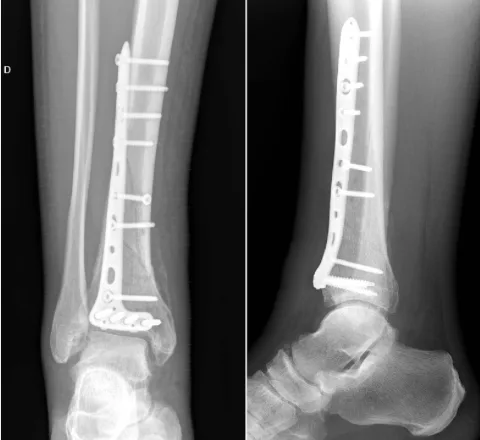

13時半から, 後輩医師の執刀で脛骨遠位部骨折の手術があるため, 5分で昼食を摂って, 手術部に.

本日の手術は, 43A2.3でした.

脛骨骨折のAO/OTA分類は, 43A2.3でした.

骨折部を展開して, 元の形に戻しましたが, 腓骨は骨折しておらず, 短縮した脛骨を元の形に戻すのに難渋しました.

脛骨を整復した後, チタン合金製のプレートを前から外側にかけてあてがって, ネジで固定.

後期高齢者のため骨が弱くて, ネジをたくさん入れる必要がありました.

1時間ほどかけてプレートをネジで留めたところで, あとは後輩医師に任せて, 手術部を出ました.